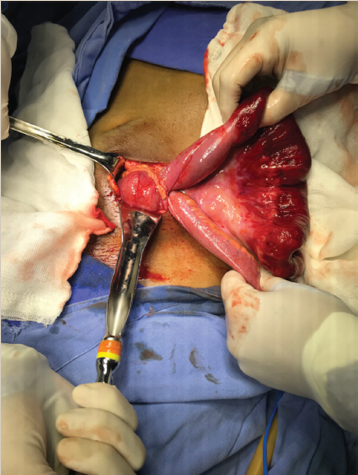

Paciente del sexo masculino, de 26 años de edad, sin antecedentes personales patológicos relevantes, que se presentó al servicio de urgencias con un cuadro de 24 horas de evolución, caracterizado por dolor abdominal en mesogastrio, tipo cólico, sin irradiaciones, EVA 10/10, acompañado de náusea y vómito, así como disminución de evacuaciones. A la exploración física dirigida, peristalsis presente, abdomen blando y depresible, doloroso a la palpación media y profunda en mesogastrio y fosa iliaca derecha. Se realizó tomografía de abdomen con contraste parenteral, en la cual se identificó escaso líquido libre en corredera parietocólica y fosa iliaca derecha, engrosamiento concéntrico de íleon de forma segmentaria, zona de transición con marcada dilatación de asas de íleon terminal (proximal al sitio de transición) (figura 1). Se inició manejo conservador con reposo digestivo con sonda nasogástrica a derivación, reposición hidroelectrolítica y antibioticoterapia, sin mostrar mejoría del cuadro clínico, por lo cual se decidió manejo quirúrgico, se realizó laparotomía exploradora y se reportaron los siguientes hallazgos; divertículo de Meckel con banda mesodiverticular que condiciona hernia interna comprometiendo asa de íleon distal de aproximadamente 25 cm (figuras 2 y 3). Se procedió a liberar asa sin lograr reversión de la isquemia intestinal y viabilidad, por lo que se realizó resección de 30 cm de íleon distal incluyendo el divertículo de Meckel, con posterior entero-entero anastomosis término-terminal, con colocación de drenaje abierto. Con adecuada evolución postquirúrgica, tolerancia a la vía oral, evacuaciones presentes, sin datos de fuga anastomótica, por lo que se decidió su egreso a domicilio al séptimo día postquirúrgico.

Figura 2 Divertículo de Meckel con banda mesodiverticular que condiciona hernia interna comprometiendo segmento de íleon terminal de aproximadamente 25 cm.